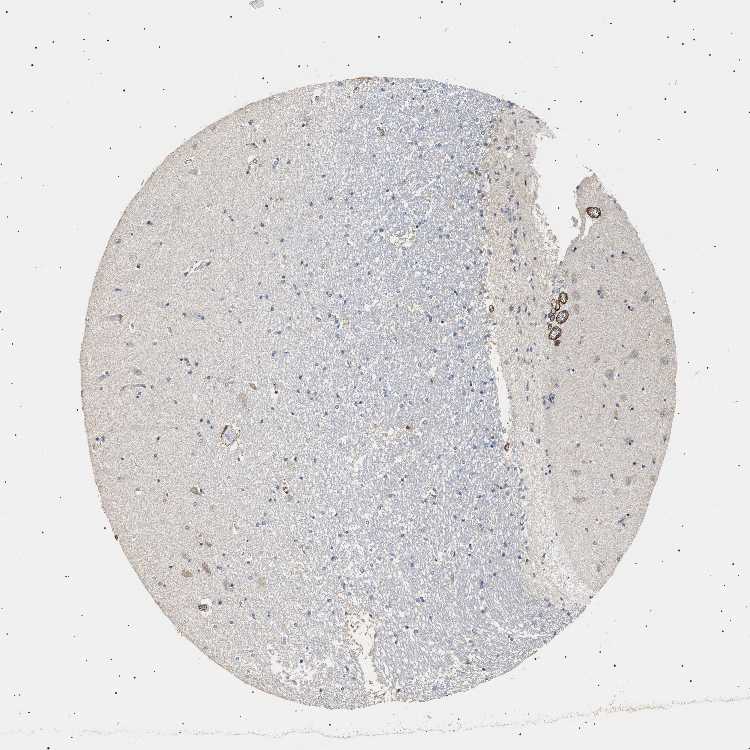

HIPPOCAMPUS - Antibody stainingi

Antibody staining in the annotated cell types in the current human tissue is reported as not detected, low, medium, or high, based on conventional immunohistochemistry profiling in selected tissues. This score is based on the combination of the staining intensity and fraction of stained cells.

Each image is clickable and will lead to virtual microscopy that enables deeper exploration of all samples and also displays staining intensity scores, fraction scores and subcellular localization as well as patient and tissue information for each sample.

Antibody HPA020386

Glial cells Not detected

Neuronal cells Not detected